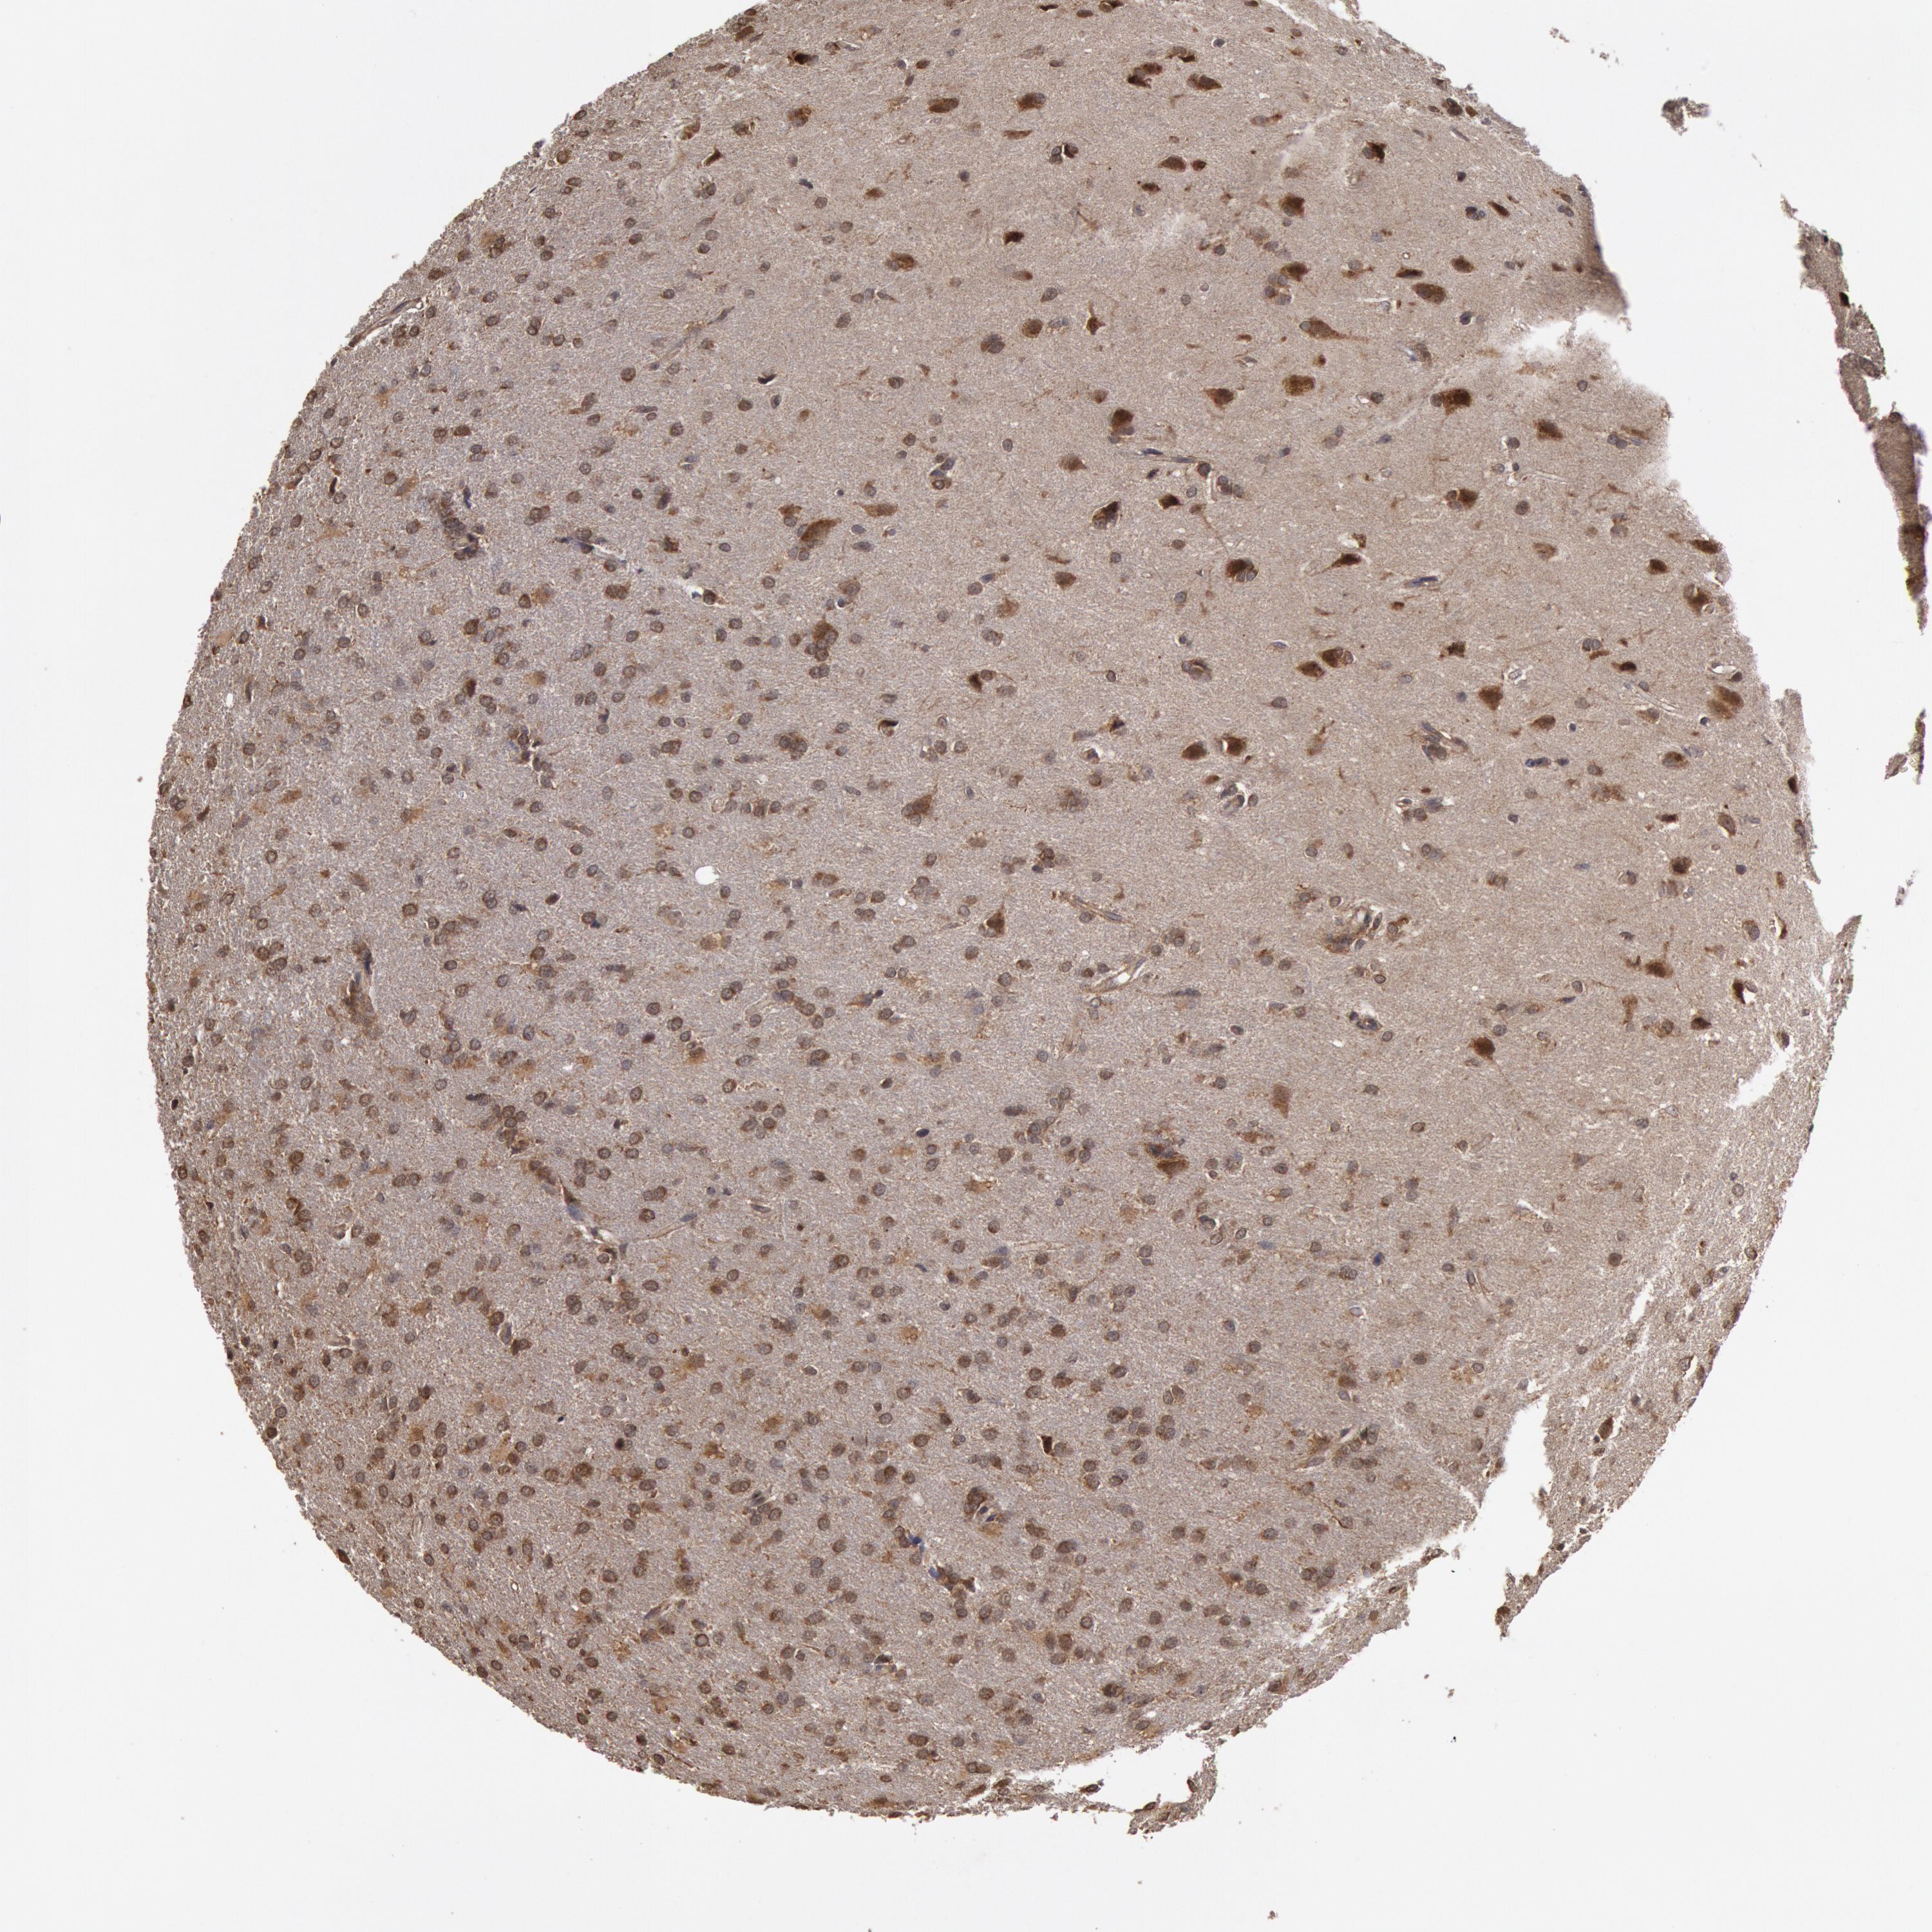

GLIOMA - Protein expressioni

A mouse-over function shows sample information and annotation data. Click on an image to view it in a full screen mode. Samples can be filtered based on level of antibody staining by selecting one or several of the following categories: high, medium, low and not detected. The assay and annotation is described here.

Note that samples used for immunohistochemistry by the Human Protein Atlas do not correspond to samples in the TCGA dataset.

Antibody stainingi

Antibody staining in the annotated cell types in the current human tissue is reported as not detected, low, medium, or high, based on conventional immunohistochemistry profiling in selected tissues. This score is based on the combination of the staining intensity and fraction of stained cells.

Each image is clickable and will lead to virtual microscopy that enables deeper exploration of all samples and also displays staining intensity scores, fraction scores and subcellular localization as well as patient and tissue information for each sample.

Antibody HPA001308

Staining

High

Medium

Low

Not detected

Intensity

Strong

Moderate

Weak

Negative

Quantity

>75%

75%-25%

<25%

None

Location

Nuclear

Cytoplasmic/membranous

Cytoplasmic/membranous,nuclear

Glioma, malignant, High grade

Glioma, malignant, Low grade